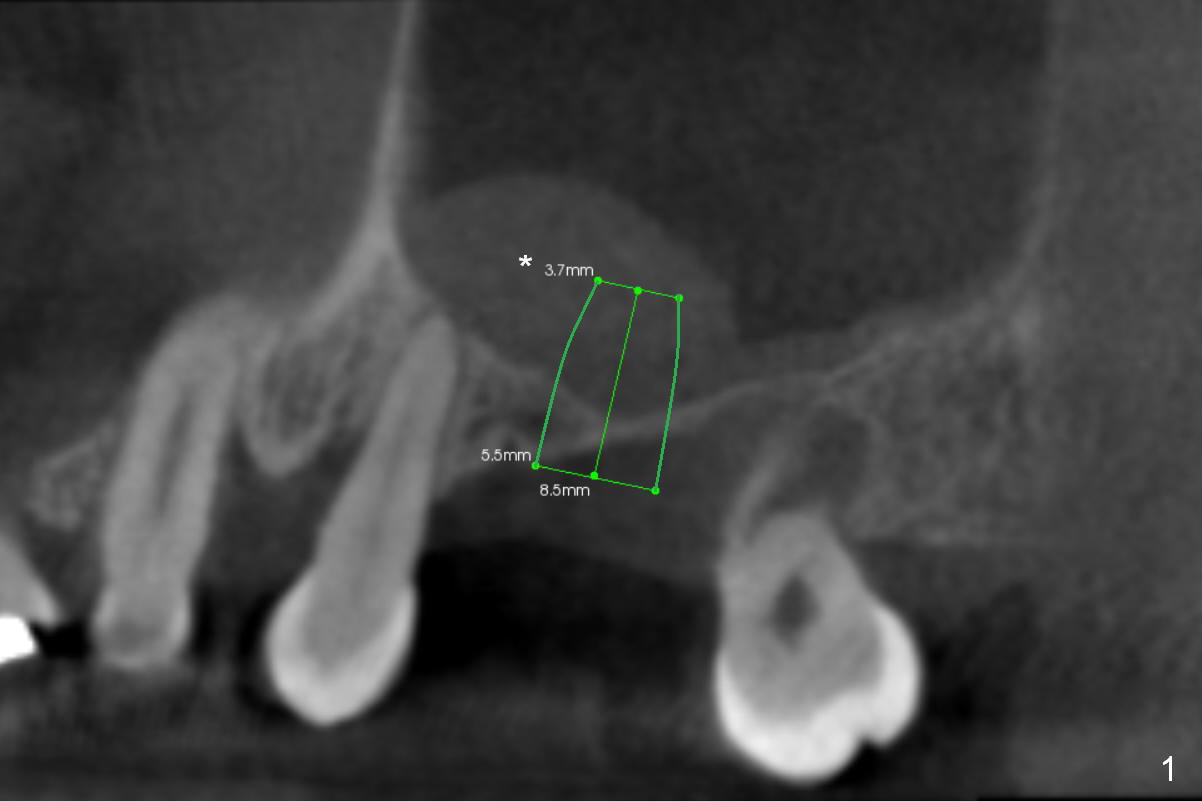

Implant in Thin Sinus Floor

A 48-year-old lady has severe bilateral sinus pneumotization, especially at the right 1st molar (Fig.1 CBCT). The sinus floor is 2 mm thick (Fig.2 coronal section). Sinus lift may require lateral window approach (Fig.2 B (buccal). Implantation may be accomplished at the same time (Fig.1). * in Fig.1: mucocele; < in Fig.2: possible perforation. An implant will be placed at #31 later.